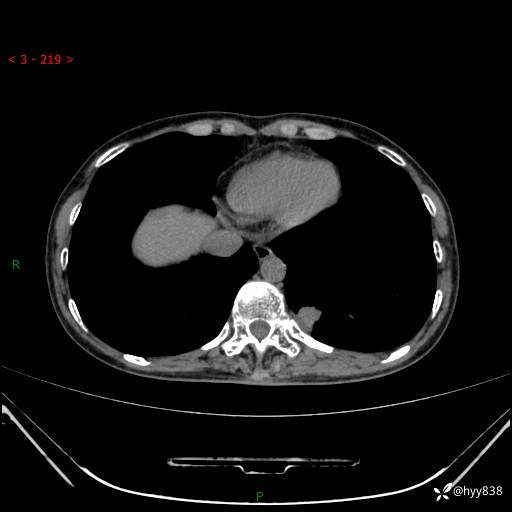

胸部CT平扫

增强动脉期+静脉期

各期CT值:48hu 65hu 76hu